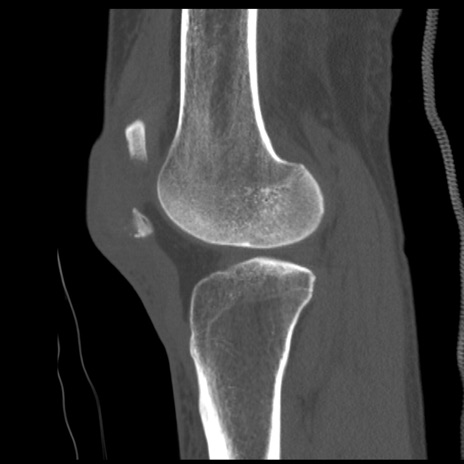

症例28 右膝関節CT(矢状断像)

右膝関節CT